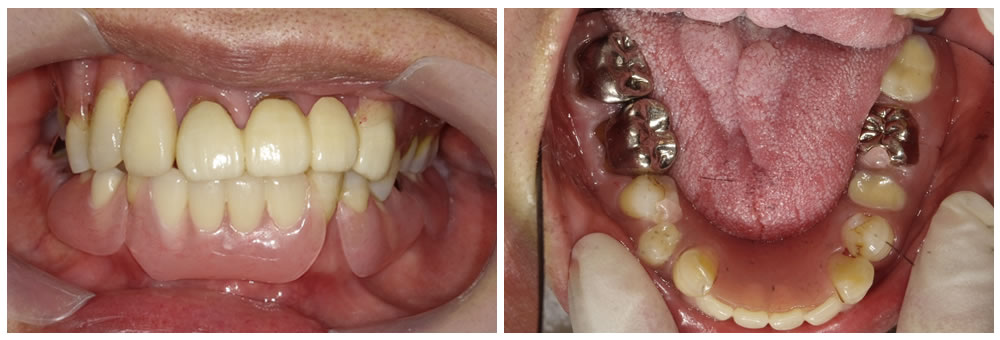

ノンクラスプデンチャーをお口に装着

ノンクラスプデンチャーがお口に入った状態です。金具が無くなったことで、見た目が自然になりました。また、残っている歯にもきれい適合し、入れ歯が安定して話もしやすく、食事の際にも痛みが出なくなったと大変喜んでおられました。今後は入れ歯と残った歯が長持ちするように、入れ歯の調整と歯周病の治療を定期的に行っていくことになりました。